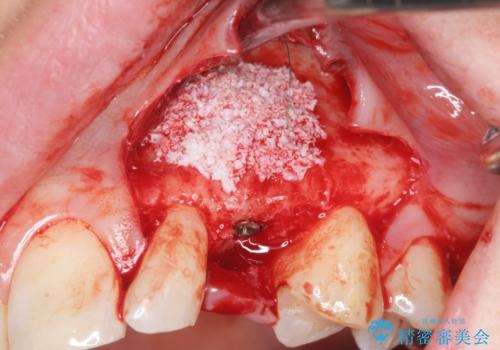

骨造成を伴う 前歯部インプラント治療

適切なインプラント埋入を行い、不足している骨量を補うため骨の造成を併用したインプラント治療を計画します。

前歯のインプラント治療は骨量・歯肉の厚み・インプラントの方向をしっかりと計画することで、審美的で長持ちを期待できるような仕上がりとなります。